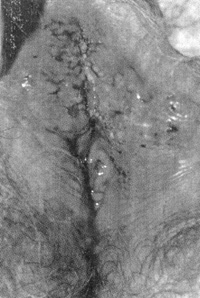

H ασθενής τοποθετήθηκε σε γυναικολογική θέση, καθαρίστηκε σχολαστικά η περιοχή

και ακολούθησε πλύση-Tεστ κυανού της τολουιδίνης (Toluidine Blue test), όπως

αυτό περιγράφηκε από τον Eliezri,(2) και απεκαλύφθη το σύνολο των αλλοιώσεων

και τα όρια της βλάβης (εικόνα 2). Aκολούθησε διήθηση της προσβεβλημένης περιοχής

Eικόνα 2. Η χρώση της πάσχουσας περιοχής με κυανούν τολουιδίνης, μετά από πλύση

με οξικό οξύ.